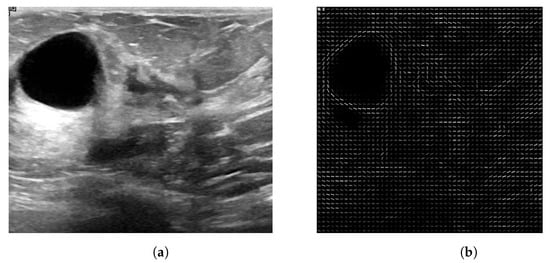

2.1. Databases Used

The Breast Ultrasound Images Dataset (Dataset BUSI) is a dataset that was collected in 2018. The collected data consist of 780 breast US images in PNG format, with size 500 × 500 pixels, including the segmentation masks belonging to 600 patients. Additionally, the images are labeled with one of three classes: normal, benign, and malignant. The database can be obtained online [22]. The mini-DDSM is a current version of the DDSM (Digital Database for Screening Mammography) and is presented in 8-bit JPEG and 16-bit PNG formats. The data are divided into normal, benign, and malignant classes. In addition, the images contain the location of a lesion. The database can be obtained from the following studies and webpage [22,23,24]. Figure 1 and Figure 2 present several examples of benign and malignant lesions from these datasets.

Obtaining the ROI image from US is more difficult due to the noise (speckle) contained and low contrast values, due to the nature of the acquisition process [11]. Moreover, the lesion is visible to the specialist due to their trained eye, so a radiologist manually cropped each image and labeled the ROI.